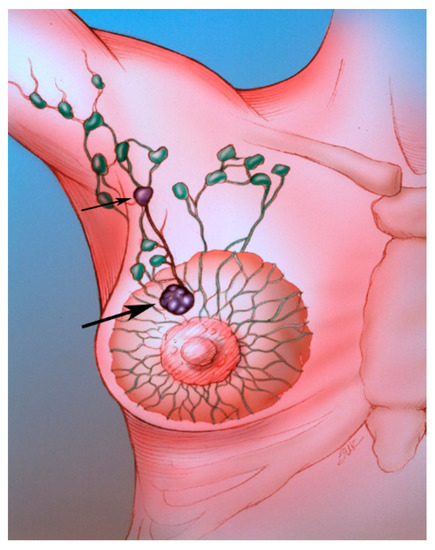

Sentinel lymph node biopsy (SLNB) has become standard in patients being treated for breast cancer with clinically negative lymph nodes [4]. The sentinel lymph node (SLN) concept (Figure 2), which states that the histologic status of the SLN is predictive of the status of the regional lymph nodes, is based on the orderly spread of tumor from the tumor bed to the regional lymph nodes. Sentinel lymph nodes (SLNs) are defined as the first group of lymph nodes draining the tumor bed. The SLNs can be located by injecting blue dye and/or radioactive material at the tumor site and subsequently, identifying a blue (Figure 3) and/or a radioactive lymph node in the axilla. Originally proposed in the management of penile cancer by Cabanas [5] in 1977, the SLN concept has been applied in patients with malignant melanoma [6] with considerable success. The American College of Surgeons Oncology Group (ACOSOG) Z011 trial compared two groups of clinical T1–2 N0 M0 breast cancer patients with a positive SLN [7]. The patients were treated with lumpectomy and opposing tangential field radiation therapy and adjuvant systemic therapy at the discretion of the treating physician. One group was randomized to SLNB without axillary dissection. The other group was randomized to SLNB followed by completion axillary dissection. The SLNB only group did not show inferior survival rates compared to the axillary lymph node dissection group [7].

Figure 2. The SLN (small arrow) is the first lymph node draining the tumor (large arrow).